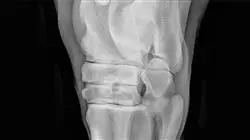

Se vuoi diventare un esperto nella diagnostica per immagini di patologie muscoloscheletriche, il nostro Corso Universitario di TECH Global University è la scelta ideale per te. Qui ti offriamo l'opportunità di immergerti nel campo emozionante della diagnostica per immagini e imparare a diagnosticare e valutare varie patologie muscoloscheletriche. Attraverso il nostro programma di lezioni virtuali, avrai accesso a contenuti accademici di qualità e sarai guidato da esperti nel campo dell'imaging. Per 1-3 mesi, esplorerai le tecniche di diagnostica per immagini più avanzate applicate alle patologie muscoloscheletriche. Imparerai come interpretare radiografie, risonanze magnetiche, tomografie computerizzate e altri strumenti di imaging per identificare e valutare lesioni, malattie e disturbi del sistema muscolo-scheletrico.